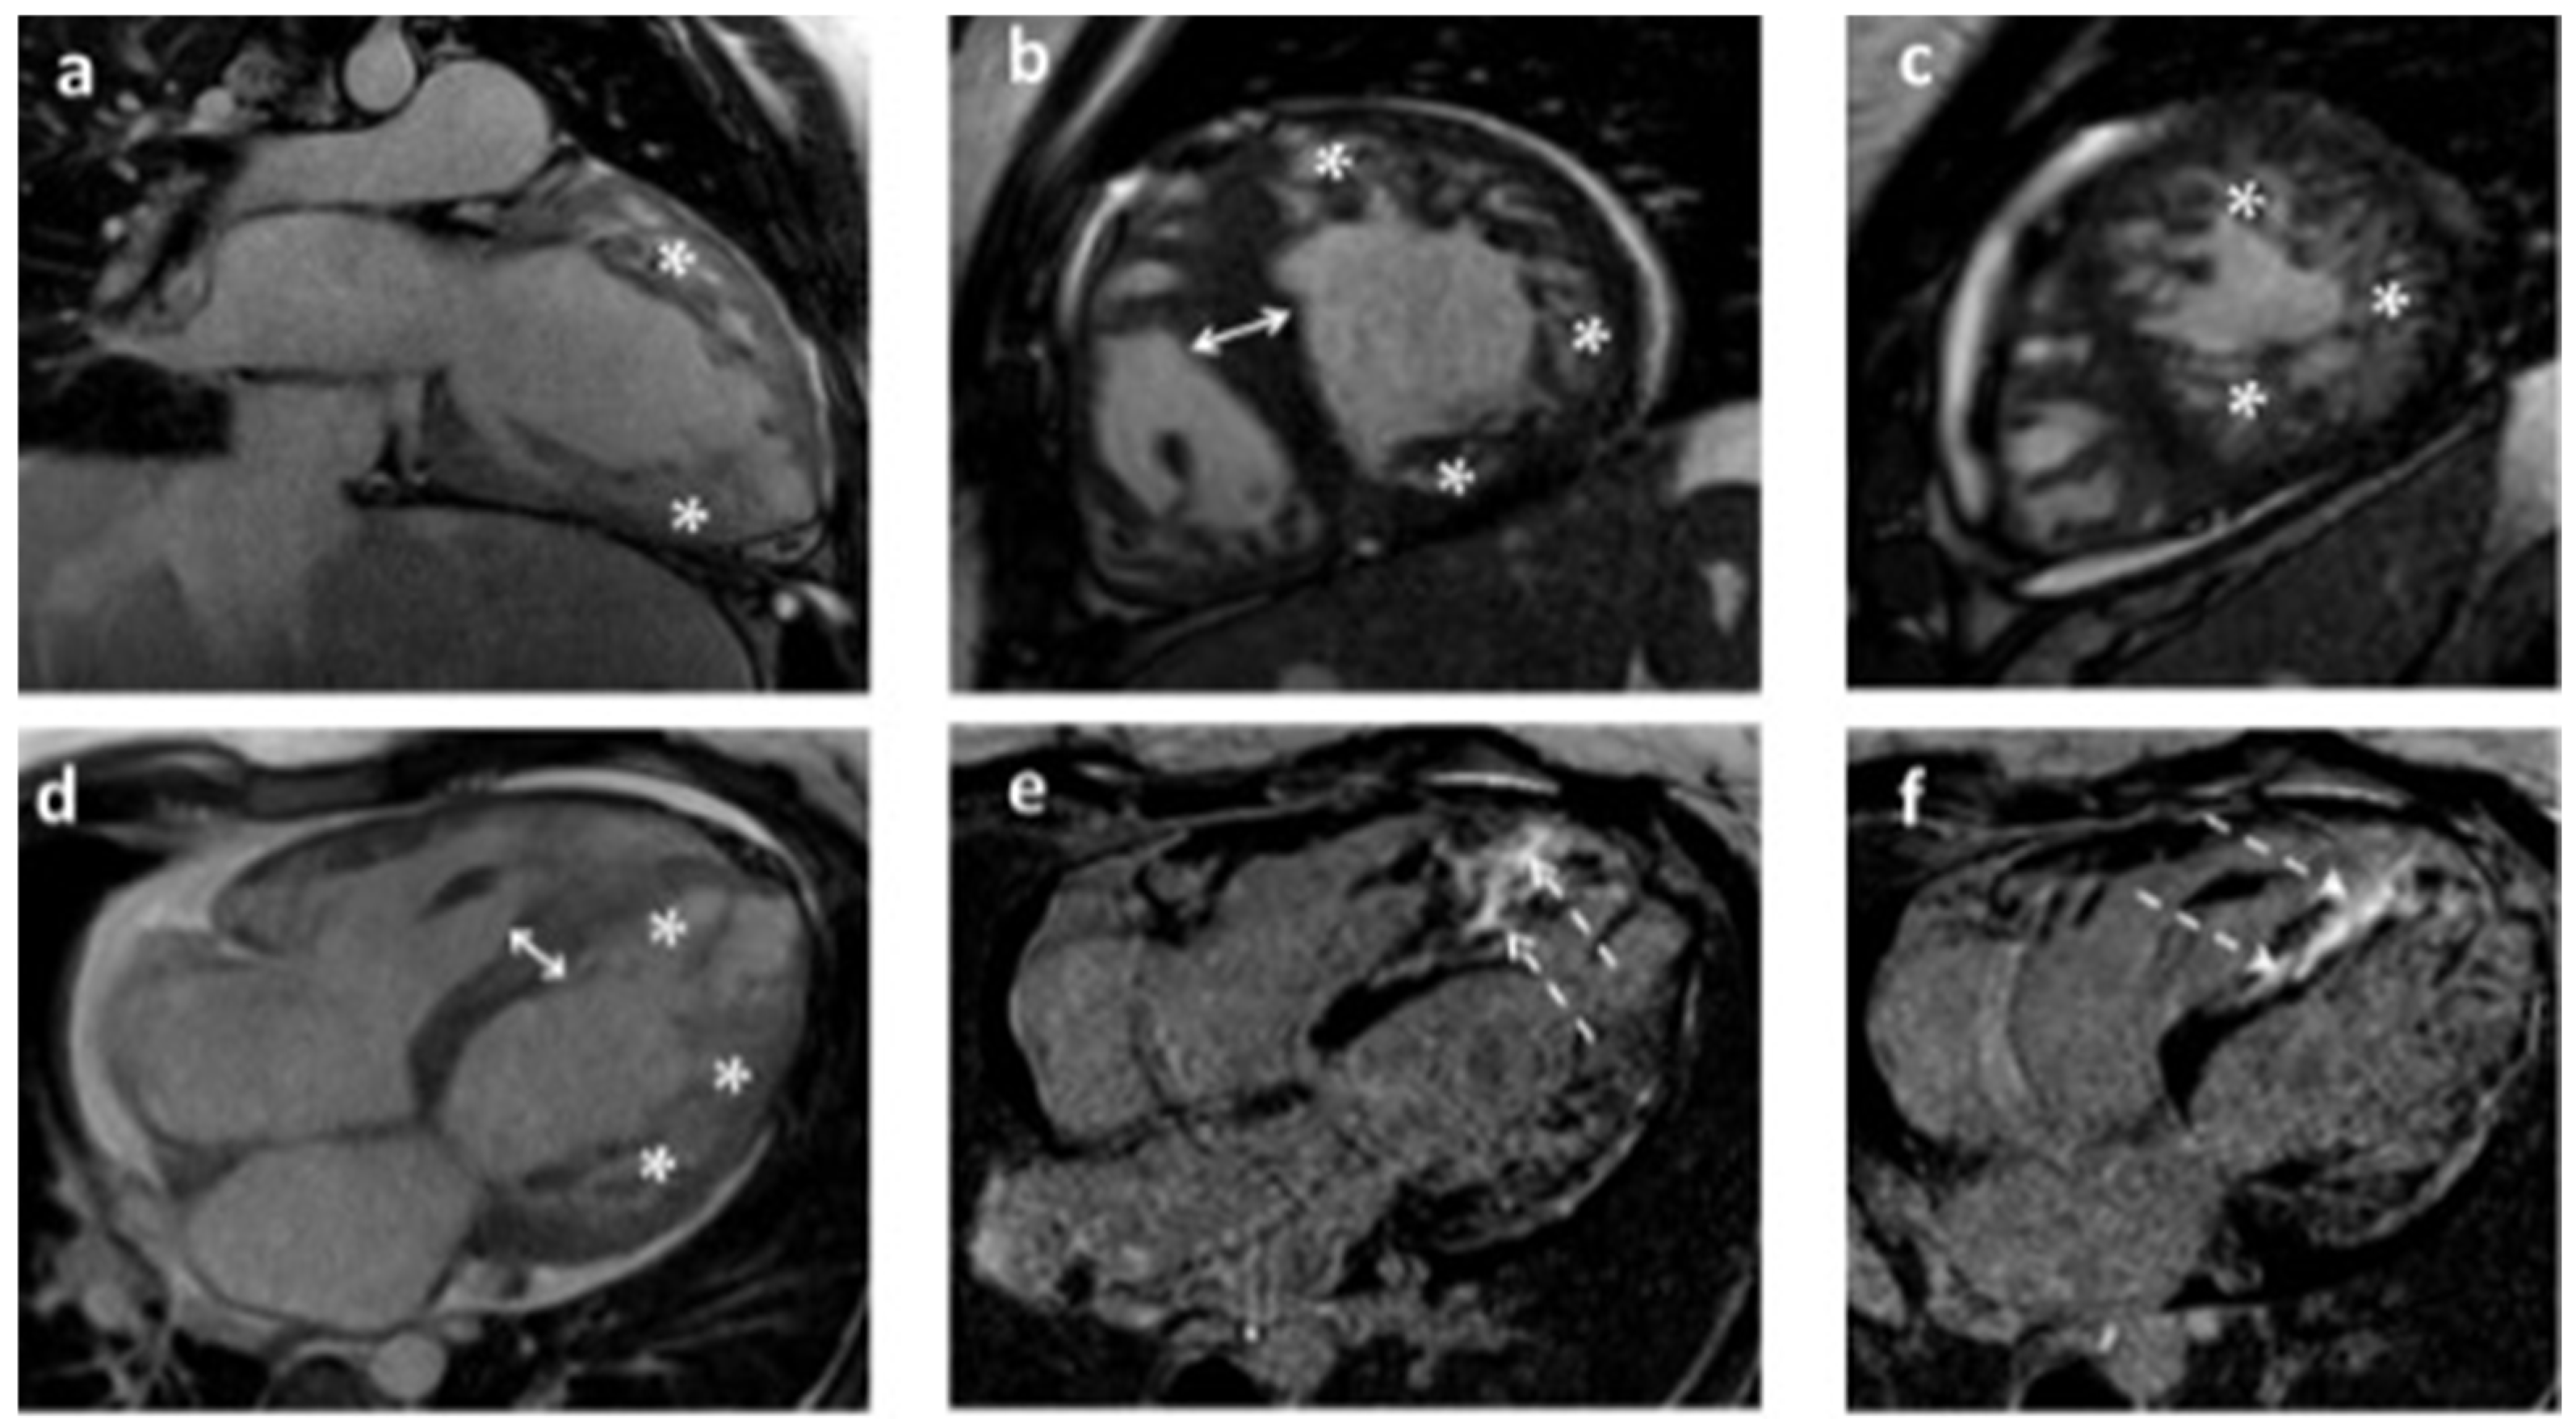

2. Detailed Case Description

2.1. Clinical Presentation